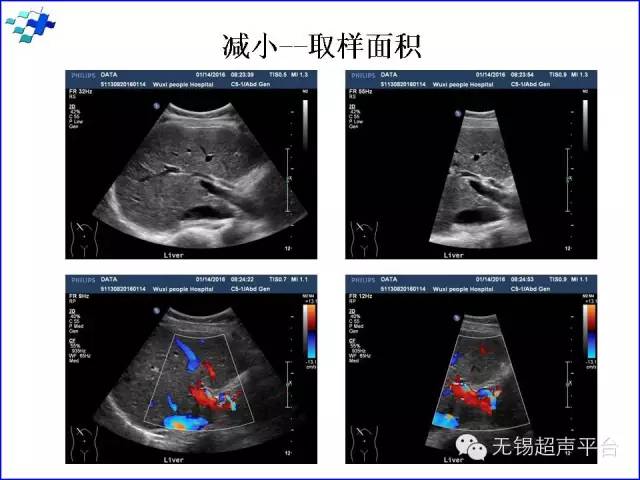

宽度(width):图像的宽度越大局部取样线密度越稀疏,帧频越低。图像放大(zoom):感兴趣区域的放大功能,对相对较小的结构和快速运动的结构的评价有很大价值,如瓣膜的形态学。